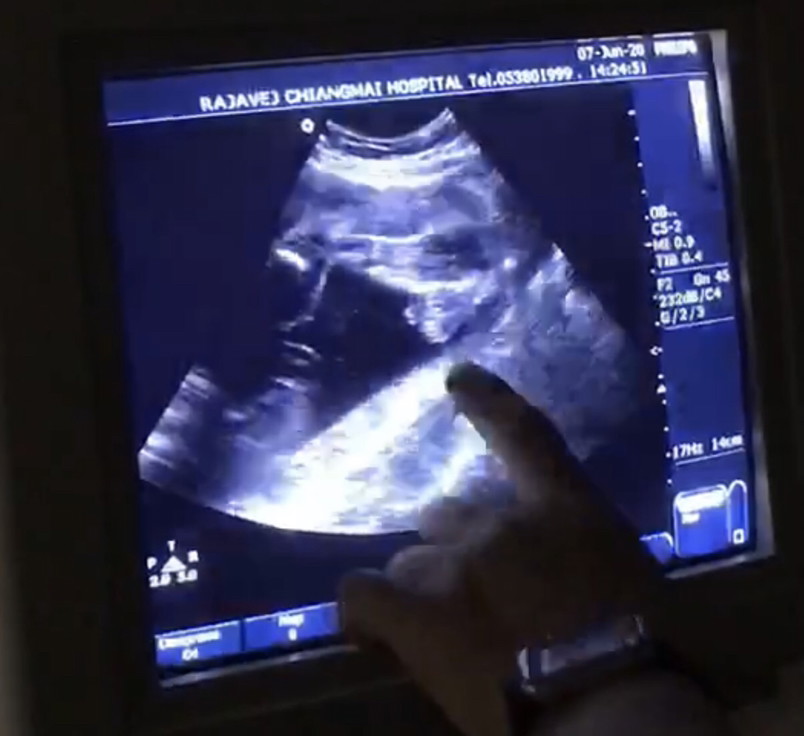

ยังงี้มองออกไหมคะ ว่าเพศอะไร

ช่วยดูหน่อยคะแม้ว่า บ้านนี้หญิงหรือชาย

หมอไม่ชัวร์ แม่ๆว่าหญิงหรือชายค่ะ